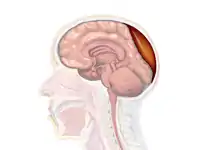

Non-contrast CT scan of a traumatic acute hematoma in the right fronto-temporal area. A diagram showing an epidural hematoma.

A diagram showing an epidural hematoma.